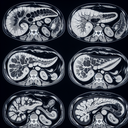

Магнітно-резонансна томографія (МРТ) органів черевної порожнини – це неінвазивний метод діагностики, який використовує магнітні поля та радіохвилі для отримання детальних зображень внутрішніх органів і структур живота. Цей метод допомагає виявити різні патології та стану, включаючи пухлини, запалення або інфекції. Основні переваги МРТ органів черевної порожнини: - Висока точність і деталізація зображень...

МРТ печінки – це неінвазивний метод діагностики, який використовує магнітне поле та радіохвилі для створення детальних зображень печінки. Цей метод дозволяє виявити різноманітні захворювання та стани, такі як пухлини, кісти, жирові зміни або запалення. ### Переваги МРТ печінки: 1...

Магнітно-резонансна томографія (МРТ) селезінки — це неінвазивний метод діагностики, що використовує магнітні поля і радіохвилі для отримання детальних зображень селезінки. Цей тест особливо корисний для оцінки структури, виявлення аномалій, пухлин, кіст або пошкоджень, а також для оцінки кровотоку. МРТ селезінки може бути призначено у таких випадках: 1...

МРТ підшлункової залози – це неінвазивне дослідження, яке використовує магнітні поля та радіохвилі для отримання детальних зображень органу. Це обстеження допомагає виявити різноманітні патології, такі як пухлини, запалення, кісти або структурні аномалії. Переваги МРТ підшлункової залози: 1...